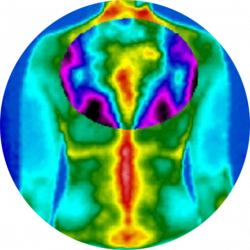

Az élő szervezet élettani folyamatait jellegzetes hőmérsékleti mintázatok kísérik. Gyulladásos folyamatok, keringési eltérések vagy fokozott anyagcsere-aktivitás esetén a test felszínén mérhető hőmérséklet megváltozhat.

A digitális orvosi termográfia ezeket az eltéréseket rögzíti egy nagy pontosságú infrakamera segítségével, majd vizuális hőtérképen jeleníti meg. Az így kapott információk értékes kiegészítést nyújthatnak az egészségi állapot felmérésében.

Infrakamerával meghatározott távolságból felvételeket készítünk, melynek során a test által kibocsátott hőmérsékleti különbségekből hőtérkép készül